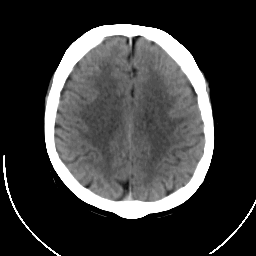

CT Study #1 -- Slice #16